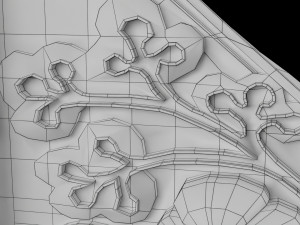

Breast anatomy histology detailed labelled precise to scale model 3D Модель

This is a 1:1 scaled model of right breast cut opened in sagittal plane to reveal its internal antomy and histology (schematic). The deeper parts and fascial layers are also depicted to give a very detailed approach to the model. The full layers starting from skin, nipple areola, till intercodtal muscles and ribs are also depicted.